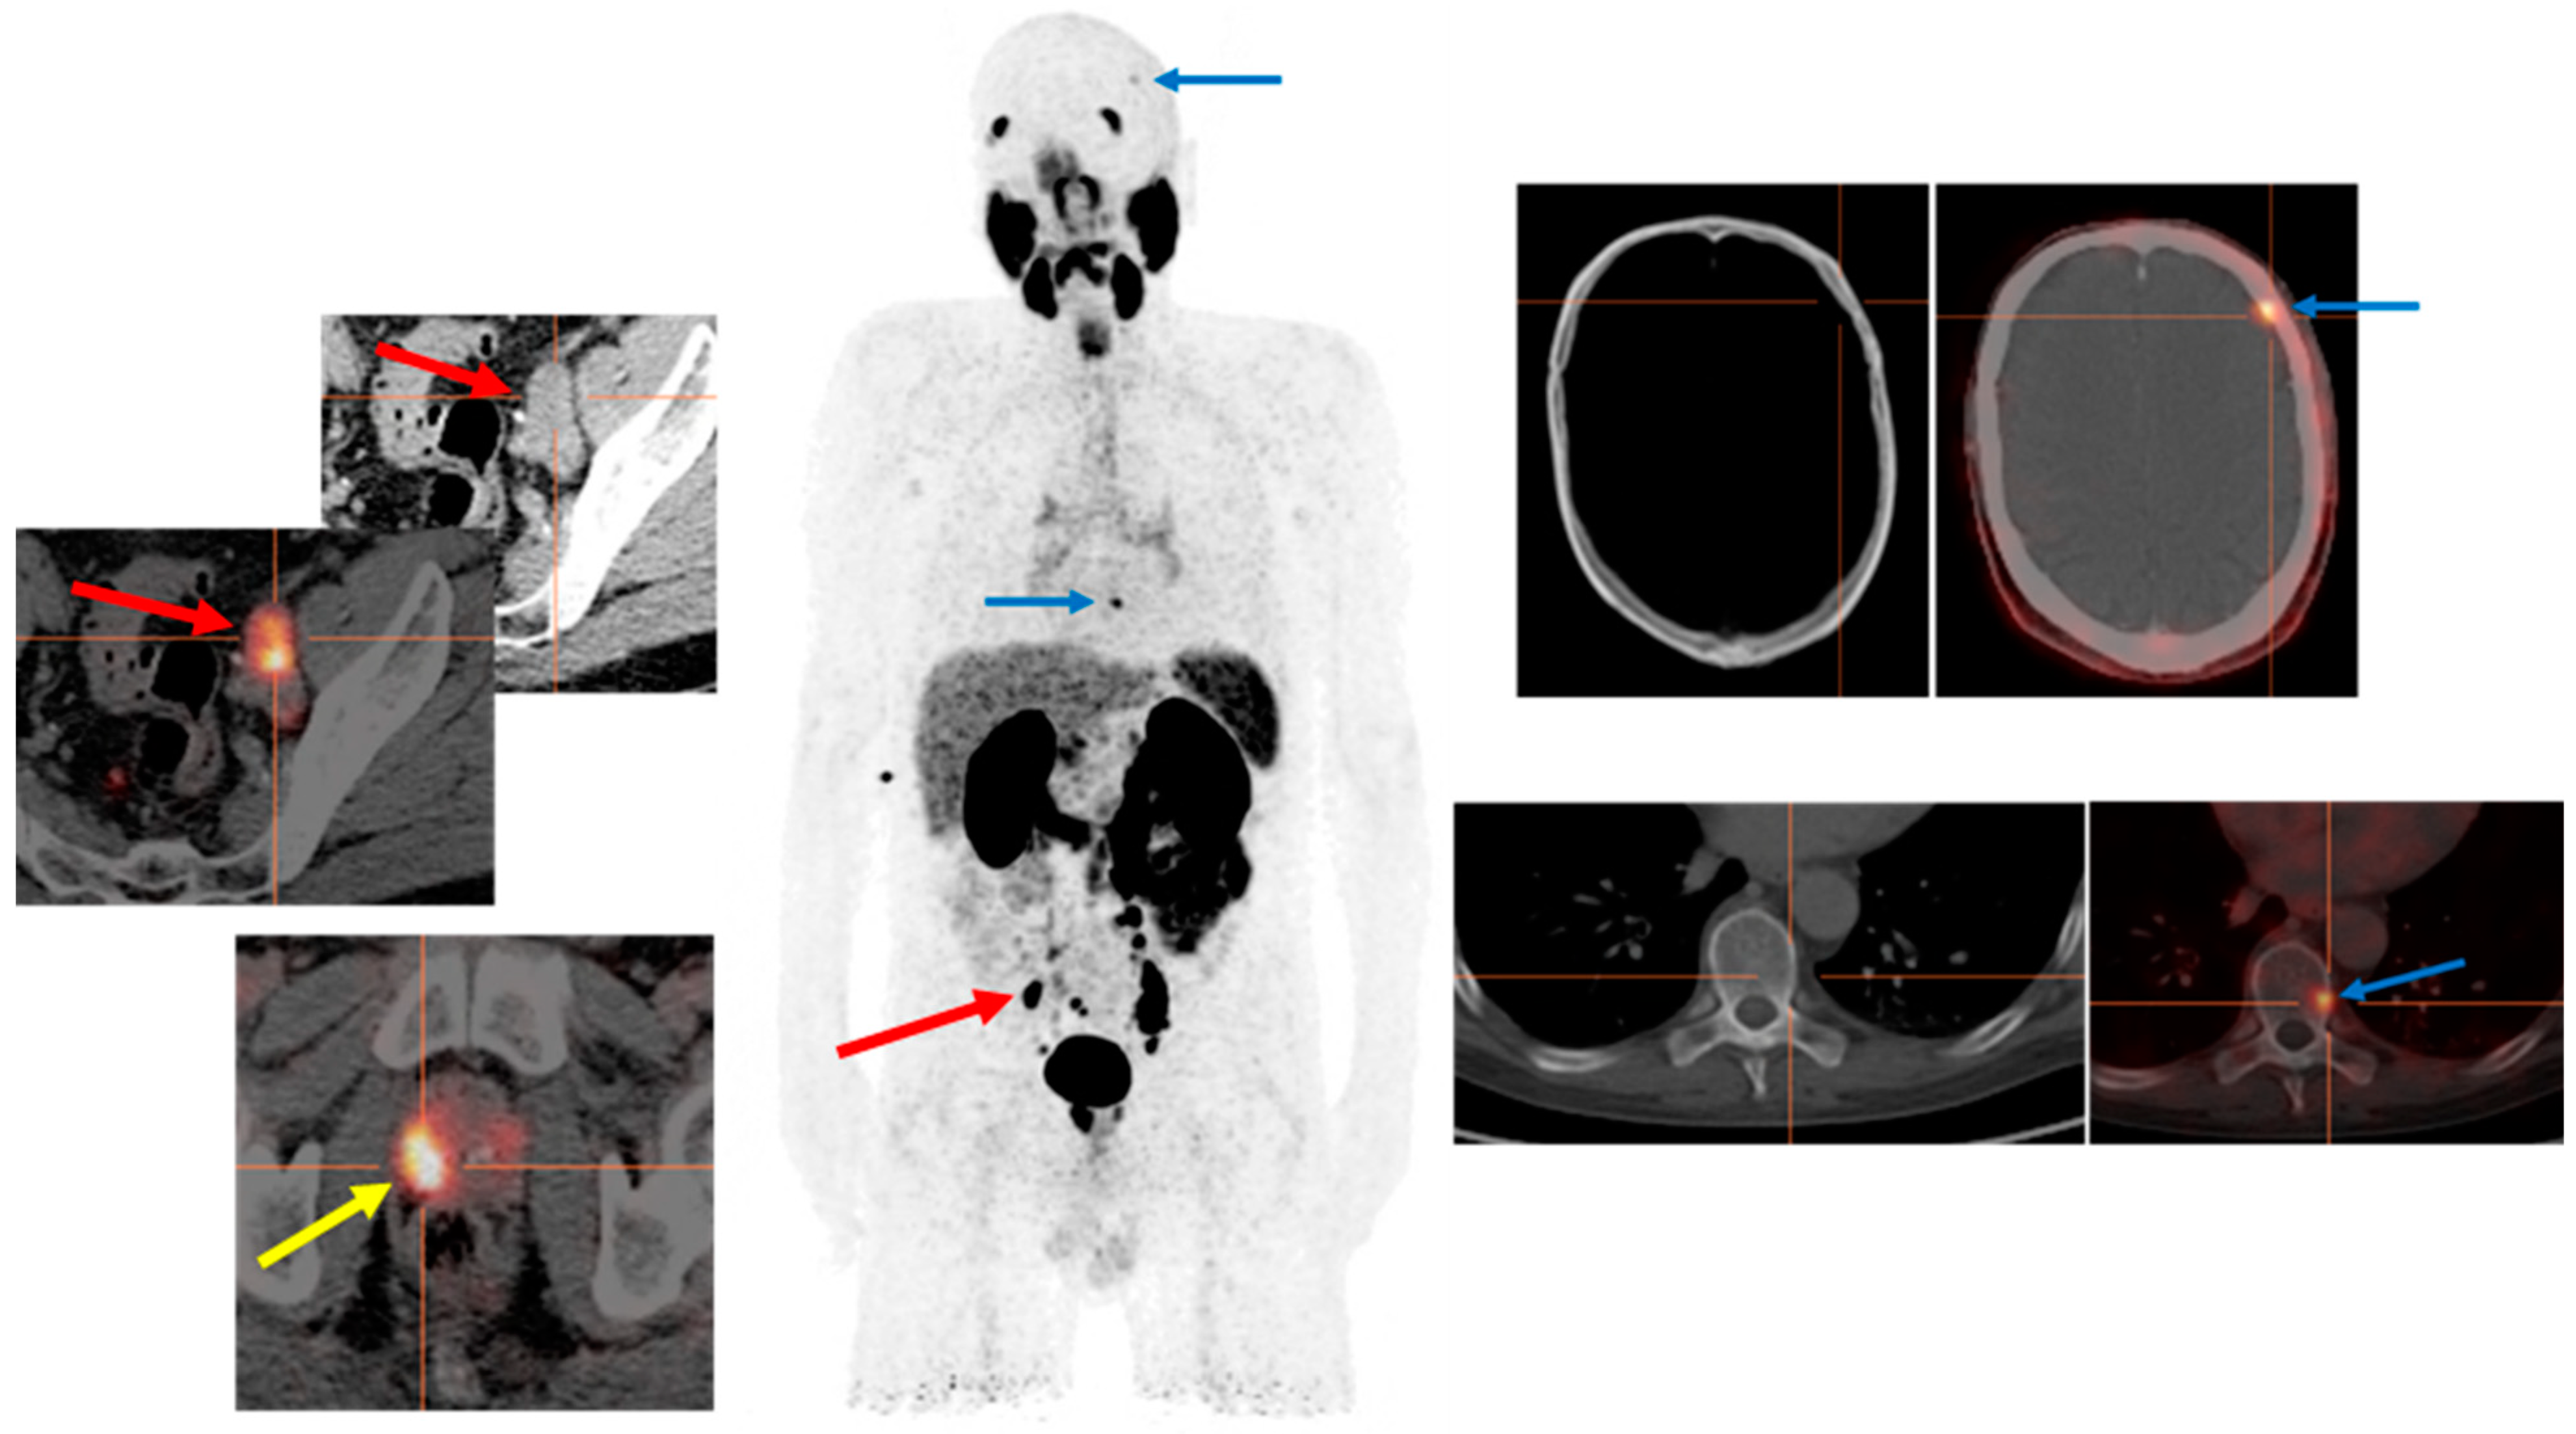

2. Clinical Report of the PSMA PET Scan

3.2. PSMA PET in Biochemical Recurrence PCa

3.3. Evaluation of PCa Patients for Possibility of PSMA Radioligand Therapies